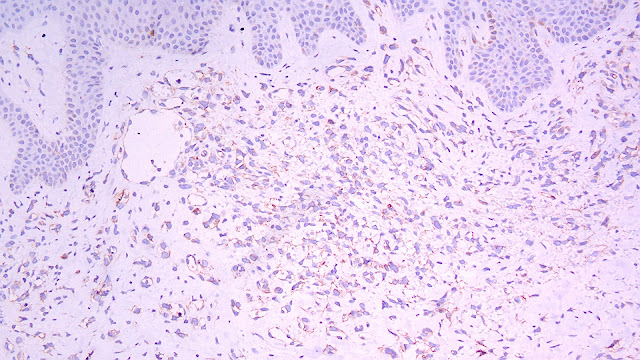

Biopsia de piel:

Biopsia

Canales vasculares anormales y anastomosados

Los bordes son infiltrantes y no están bien circunscritos

En los tumores poco diferenciados, puede haber áreas sólidas fusiformes o epitelioides sin formación evidente de vasos.

Un panel de marcadores de antígenos endoteliales y epiteliales puede ayudar a distinguir el AS del carcinoma poco diferenciado